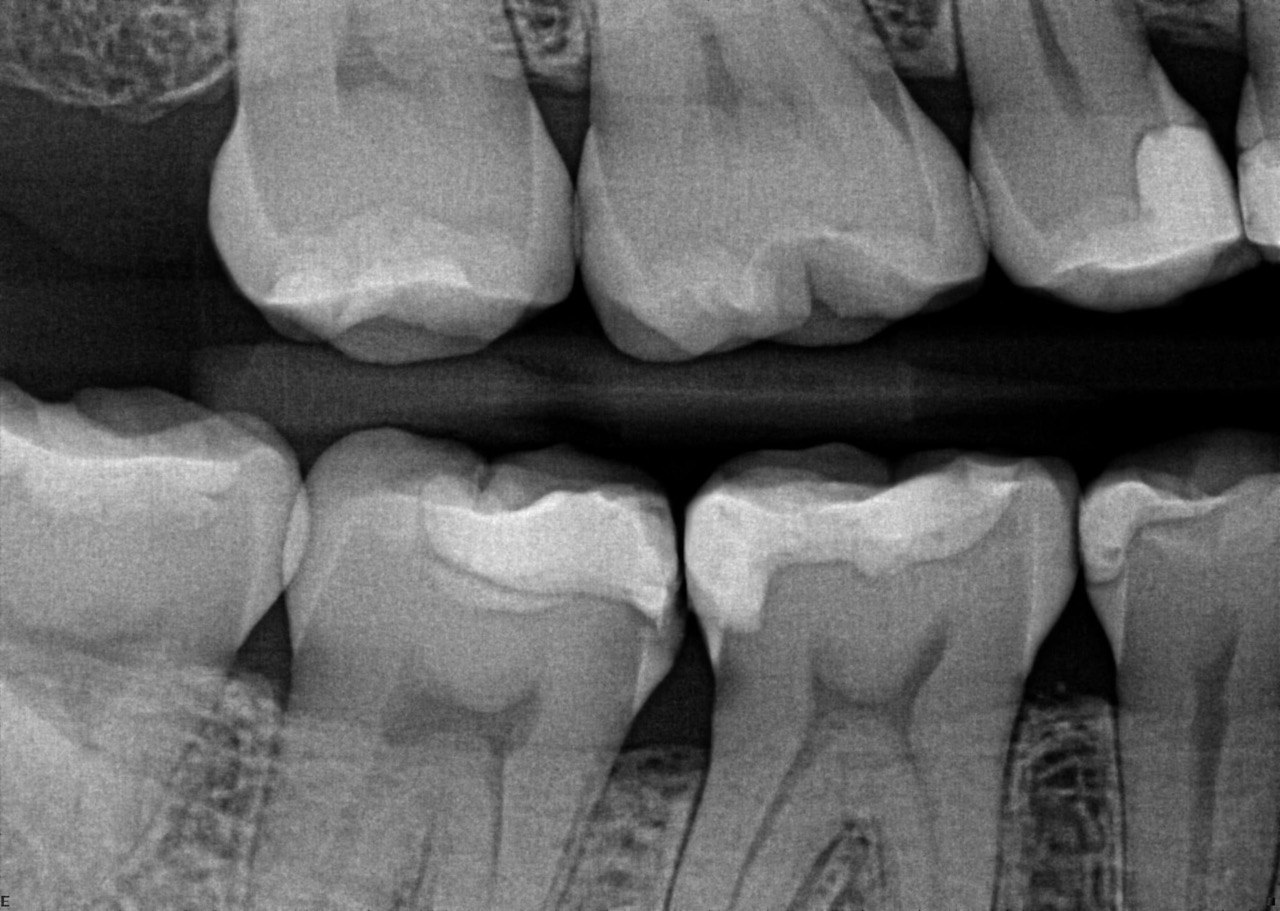

1. Which surfaces shows dental caries?

2. Which surface needs restoration?

4. Which surface needs restoration?

5. Which surface needs restoration?

8. Which surface needs restoration?

18. Which surfaces need restoration?

32. Which surfaces needs restoration?